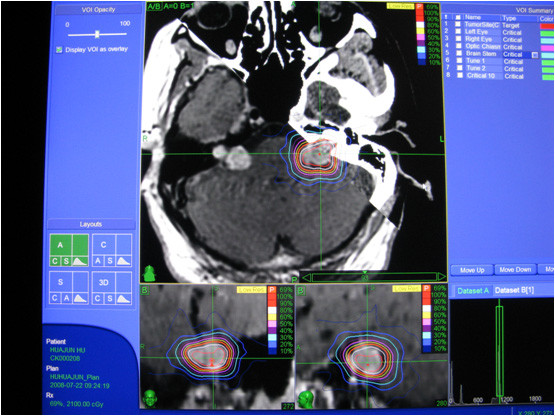

腹膜后肿瘤病例报告

2023-12-27 | 发布者:admin | 查看数:6175